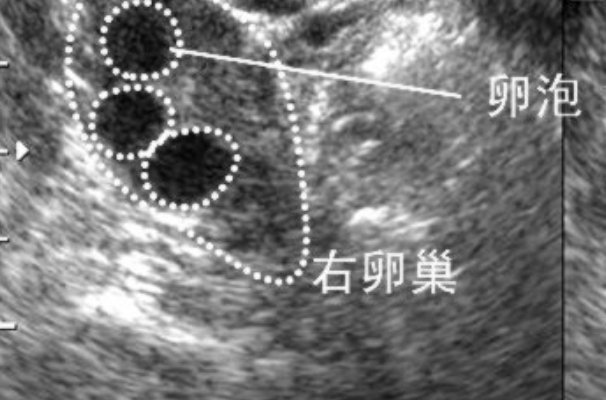

在民间说法和网络传言中,一直流传着"右侧卵泡排卵后怀孕就会生男孩"的观点,这一说法常被不少备孕家庭津津乐道,甚至有人刻意通过监测排卵侧来试图选择胎儿性别。然而,从现代生殖医学和生物学的角度来看,这种关联缺乏严谨的科学依据,更多是基于偶然概率或传统经验的过度解读。胎儿的性别本质上是由遗传物质决定的,而非母体排卵的左侧或右侧位置。

卵泡只是卵子的"住所",而卵子本身并不携带决定胎儿性别的染色体。胎儿的性别是由精子的性染色体(X或Y)与卵子(X染色体)结合时随机决定的。右侧卵泡排卵仅表示本次排卵发生在右侧卵巢,这与性别选择毫无关系。

答案是否定的。卵泡位于左侧或右侧卵巢,仅仅是生理上的随机现象。女性卵巢通常交替排卵,但哪一侧排卵并不影响卵子的遗传构成。卵子只携带X性染色体,而精子则可能携带X或Y染色体。当携带Y染色体的精子与卵子结合时,胎儿性别为男(XY);若精子携带X染色体,则胎儿性别为女(XX)。这一过程是完全随机的,与排卵侧无关。